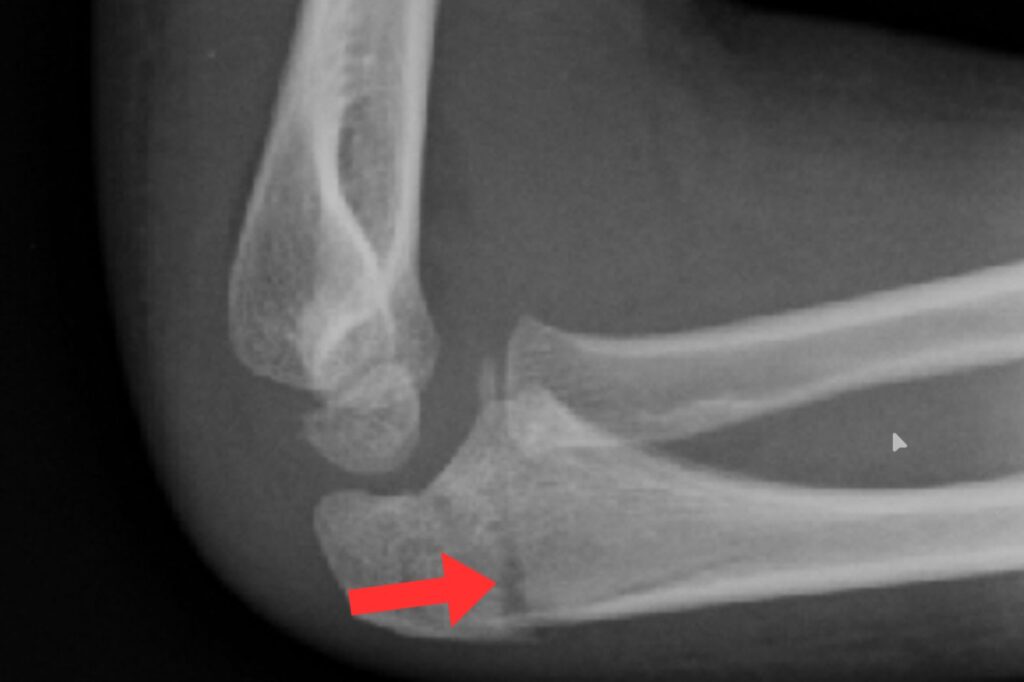

肘の後ろ側のケガ(肘頭骨端線損傷)

肘の後ろの骨端線が傷つく状態です。

- 投げた瞬間の後ろ側の痛み

- 肘が最後まで伸びない

といった症状が出ます。